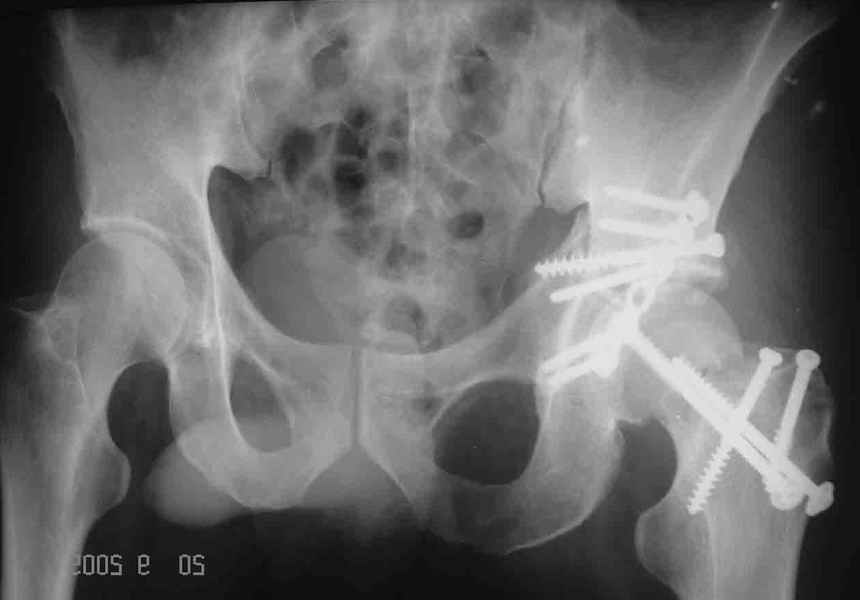

Привет! Вот недавно прооперировали похожий на ваш случай - впадина + шейка (правда у нас впадина поперечный+задний край). После травмы прошло 4 недели. мужчине 46 лет. С такой комбинацией все показания к первичному протезированию. Морально и технически мы к этому уже созрели.Но больной не собрал денег на протез. Выполнили остеосинтез впадины и шейки, прекрасно понимая, что головка вскоре рассосется, мы хотя бы надемся что к этому времени таз срастется, как говорится создали все условия для дальнейшего протезирования (может, и протез в последующем подешевле будет, в смысле, без укрепляющего кольца?). Привет Рункову!

Привет Алекей! Сделано неплохо, поздравляю, хотя второй винтик можно было бы и подлиннее в шейку загнать! Пара вопроов: доступ такой же? головка была свободной или висела на капсуле?

Согласен, можно было и подлиннее. Доступ такой же - чрезвертельный, только разрез кожи прямой (а не Y, чего то я разницы не ощущаю). Головка была абсолютно свободной (то есть во время остеосинтеза таза лежала в стакане и не мешалась). Шансов, что она прирастет 0,00001%. Хотели даже выбросить, но привинтили как временный биологический протез (читай свободный трансплантат), чтоб на период срастания таза бедро проксимально не ушло (может ортопеды потом спасибо скажут). Ну а у вас первичное протезирование при переломе впадины тоже пока полько в планах?